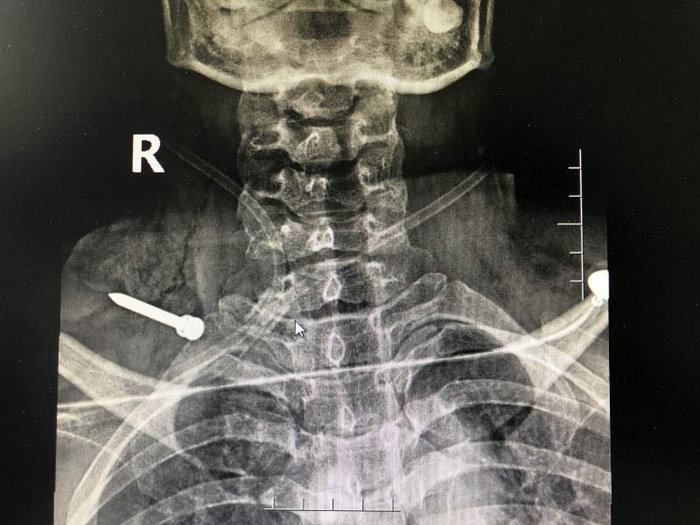

随后,王女士立即被120送往了苏州科技城医院医院急诊部。急诊医护人员先为她进行了颈部CT和X线检查,普外一科主任医师王奇与骨科副主任医师徐希斌随即也赶到了急诊进行会诊。检查发现王女士右颈部有一长约6cm的伤口,伤口处还外露着一根铁钉,铁钉尖头朝外,创口内还存在活动性出血,右侧上肢活动受限。影像资料未见明确的颈部骨结构破裂。王奇表示,需立即进行颈部手术探查,明确损伤情况,取出异物。

(铁钉所在位置)

"因为颈部被高速飞行的铁钉损伤,无法确认内部受伤情况,手术必须把颈部重要血管、神经、肌肉组织显露,查看有无损伤及仔细探查伤道。"手术中,王奇小心翼翼地将钉子取了出来,发现这是一根足足有5公分长的钉子,它造成了王女士的右臂丛神经损伤,颈外静脉断裂,颈部肌肉多处断裂,伤道紧靠劲总动脉。如果再偏一点点,王女士可能都来不及赶到医院。